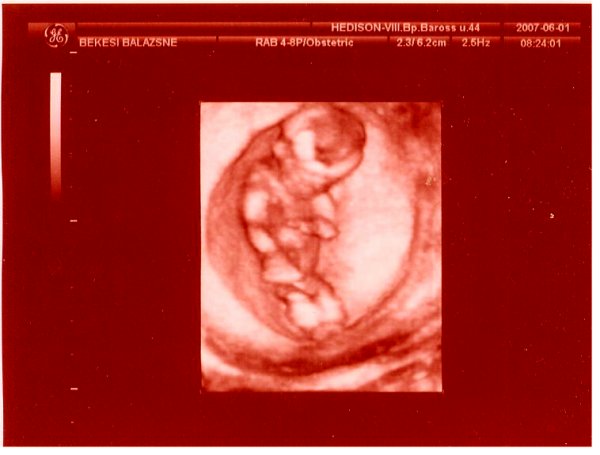

UH: befeküdt a drágánk fejfekvésbe. Ez nem is lett volna gond, ha nem a hátát és a popsiját mutatja egész uh alatt......... A kis arcocskáját befelé fordította, nem is láttuk! A doktornő is megszenvedett vele, pl. a szivecskéjét nem is tudta alaposan megnézni. Mondta neki, hogy forduljon meg, de nem hallgatott rá. Bízunk benne, hogy a jövő hét csütörtöki 4d-re megfordul, mert ha nem, hát nem sok esélyünk lesz bármire is. VAgyis semmi értelme nem lesz az uh-nak. Addig meg kell fordítanunk. Valahogy

Nemét nem akarta az orvos megmondani, mert nem nagyon volt benne biztos. Azt mondja, ha majd biztosabb lesz. Erre én rákérdeztem, hogy kisfiú? Ő visszakérdezett, hogy honnan gondolom? Mondtam, hogy megérzés. Erre ő: ő is úgy érzi. Nehéz volt megállapítani, hogy fiúcska, mert a lába közt sok volt a köldökzsinór. Megnézte áramlásmérővel, ahol volt áramlás, az a köldökzsinór volt, ahol meg nem, a kis kukija.

Itt van Ő: